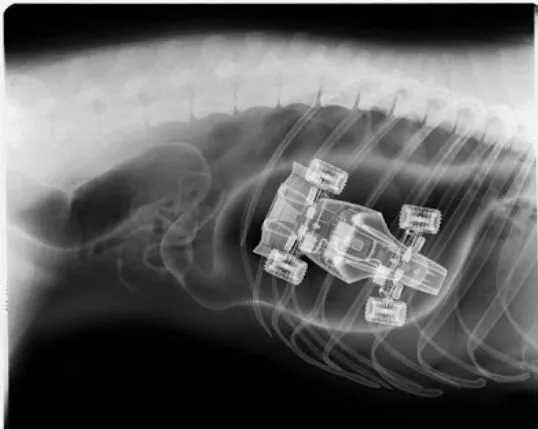

这是小孩的玩具车

这些都是在狗狗的胃里发现的,拍的X光图,看到那把刀在狗狗胃里,心里不紧张吗不担心 ,万一你家的狗狗也吃下去,想都不敢想!

狗狗似乎总是无法控制自己去吃一些没有营养价值的东西。针线、木勺、硬果壳、果核、塑料袋、珠宝、石块、抹布和袜子都有可能吃下去,狗狗胃内长期滞留这些异物不能被胃液消化,会造成胃黏膜损伤,影响胃功能。